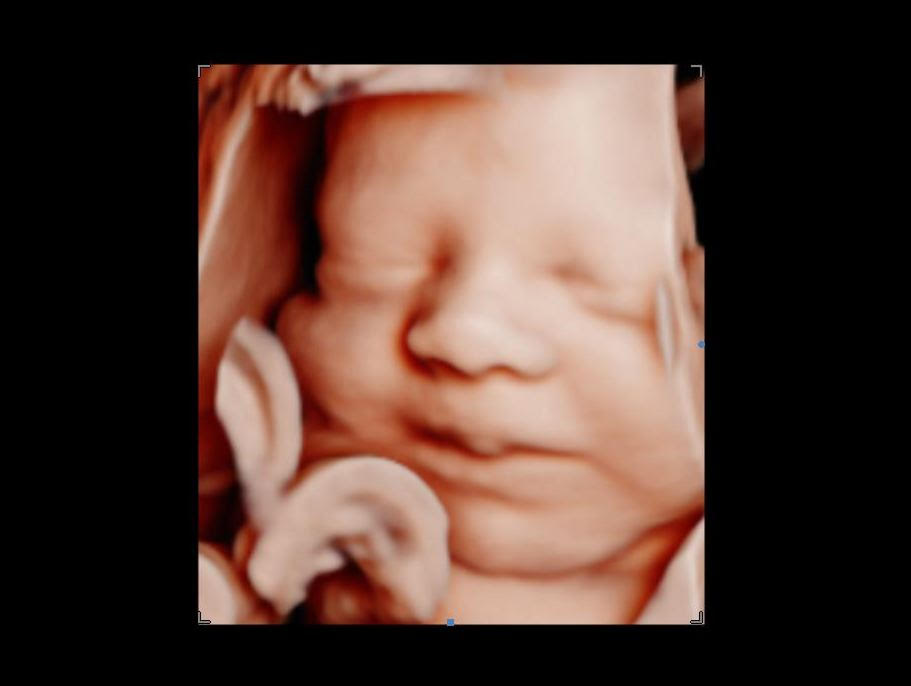

Browsing our 4D ultrasound photos gives you a clear idea of what your session can look like. You will see a range of images, from early 2D visits and gender reveal moments to rich 3D, 4D, and HD live facial detail captured during the most popular weeks between 26 and 32 weeks. Babies are unpredictable, but we have spent many sessions helping families get those sweet expressions, tiny stretched arms, and peaceful faces that you will want to hold onto for years.

Your session at Behind the Bump HD begins with your comfort. We start with 2D imaging to locate baby and find the best viewing angle, then move into 3D, 4D, and HD live ultrasound when position allows. Most visits last between 10 and 25 minutes of scanning time depending on your chosen package, and we take the time to try different positions and techniques to capture the clearest possible views.

Image clarity depends on factors like baby’s position, amniotic fluid levels, and gestational age. If your heart is set on detailed facial images, booking between 26 and 32 weeks gives you the best chance of seeing those fuller features and that characteristic stillness babies often have later in pregnancy.